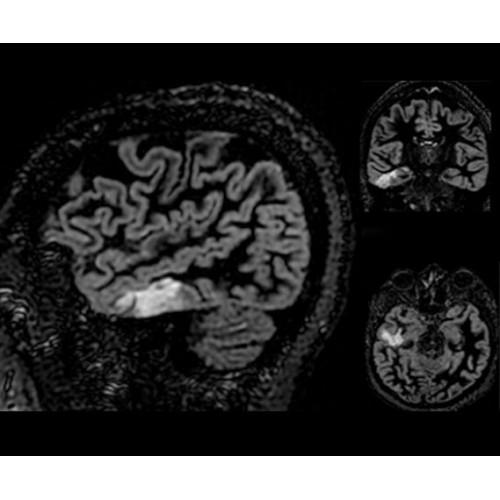

• NeuroWorks — универсальное решение для визуализации анатомии головного мозга, позвоночника, сосудов и периферических нервов с четкой дифференциацией тканей.

Поле обзора 50x50x50 см и апертура шириной 70 см позволят достоверно визуализировать сложные анатомические области для пациентов с крупным телосложением, например, плечи и бедра. Феноменальная однородность системы SIGNA Architect обеспечивает наиболее широкое поле обзора с улучшенными характеристиками градиентов. Ничто не останется незамеченным.

• 48-канальная катушка TDI для головы, входящая в базовую комплектацию SIGNA Architect, обеспечивает феноменальную производительность с учетом особенностей каждого пациента. Благодаря гибкому и универсальному дизайну, высокому соотношению сигнал/шум и передовым технологиям визуализации, таким как HyperWorks, учитываются потребности подавляющего большинства пациентов.